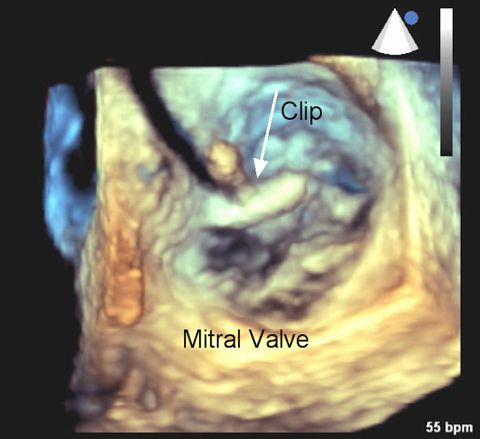

Transcatheter Mitral Valve Repair (TMVR) is indicated for patients with degenerative mitral valve regurgitation (MR) who are considered high risk for surgery. During MR, incomplete closure of the mitral valve causes blood to flow backward through the valve and into the left atrium. The 3-D echocardiogram at right shows the mitral valve leaflets from the perspective of looking downward on the valve. The clip is being put into position. (Image courtesy of Dr. Peter Rahko)

TMVR is catheter-based therapy performed using venous access and real-time imaging (echocardiography and fluoroscopy) to place the MitraClip device in the center of the valve. The device grasps and coapts the mitral valve leaflets, resulting in fixed coaptation of the mitral leaflets throughout the cardiac cycle. The device gained FDA approval in 2013. More than 1,200 patients in the United States have been treated with this procedure in clinical studies, with 1-year follow-up in over 900 patients. Over 35,000 patients have been implanted with the device worldwide.